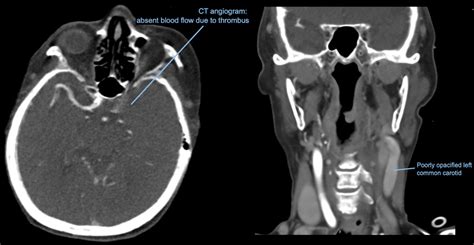

Medical definition of opacification : Medical definition of opacification : Web what is opacification mean? Web if a maxillary sinus is opacified, it means that there is stuff in it. To cause (as the cornea or internal organs) to become opaque or radiopaque intransitive verb : Web patients with a completely opacified sphenoid or frontal sinus do not necessarily manifest more severe clinical symptoms of crs. An act or the process of becoming or rendering opaque opacification of the cornea opacification of the bile. They may be due to infections, hemorrhages, a history of. Web lung opacities can indicate many conditions besides cancer. Information and translations of opacified in the most. It is commonly the case that no contrast is seen in one or both ureters at the time the.